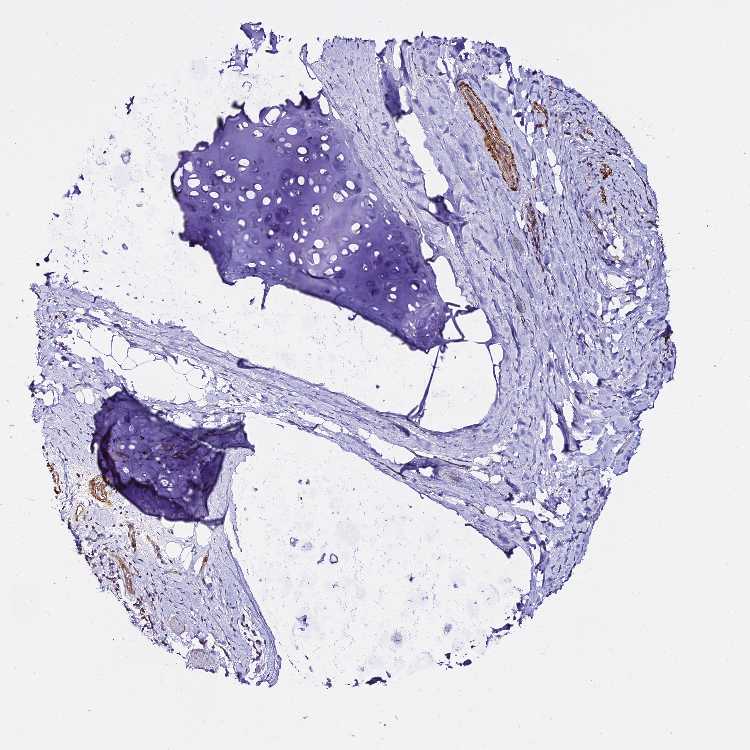

SOFT TISSUE 1 - Antibody stainingi

Antibody staining in the annotated cell types in the current human tissue is reported as not detected, low, medium, or high, based on conventional immunohistochemistry profiling in selected tissues. This score is based on the combination of the staining intensity and fraction of stained cells.

Each image is clickable and will lead to virtual microscopy that enables deeper exploration of all samples and also displays staining intensity scores, fraction scores and subcellular localization as well as patient and tissue information for each sample.

Antibody HPA045617

Chondrocytes Not detected

Fibroblasts Not detected

Peripheral nerve Not detected

SOFT TISSUE 2 - Antibody stainingi